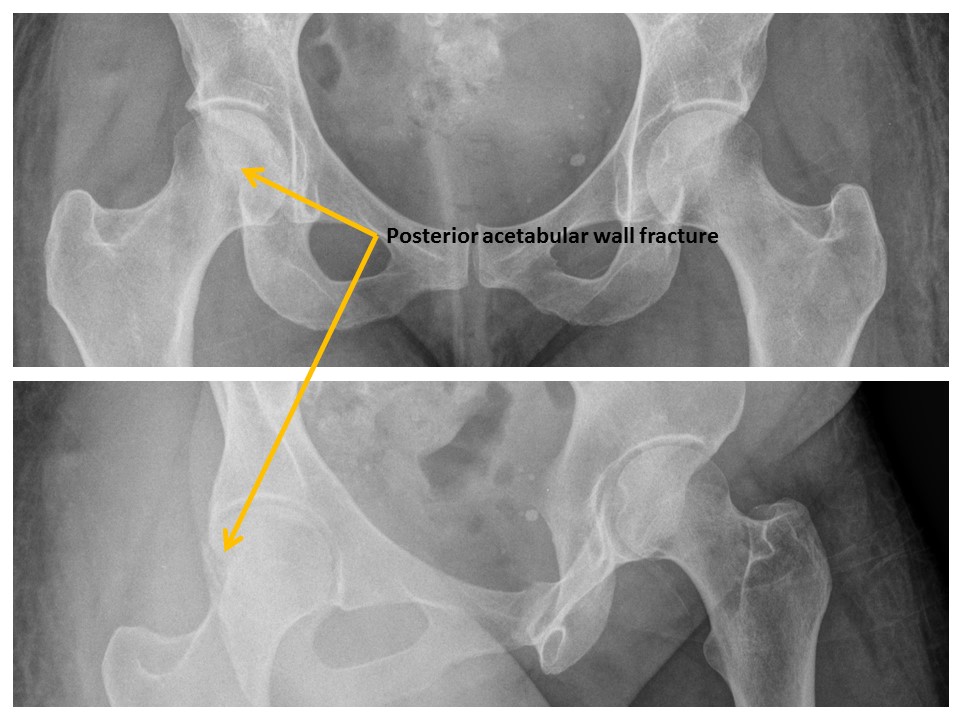

Posterior walls of the acetabula are disrupted. [Yes/No]